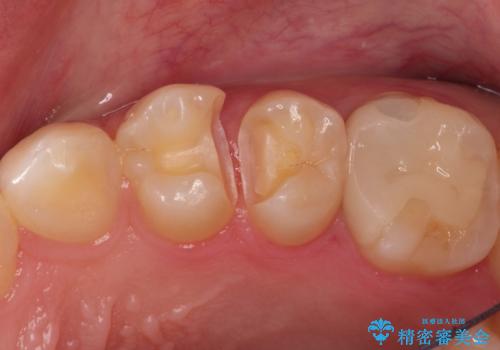

精密なむし歯の治療 セラミックインレー

- 定期健診にてむし歯を認めた患者さまです。

笑った時に見える部分だったためセラミックインレーにて修復しました。

保険治療で使える材料には制限があり、見た目だけでなく精度でも劣ります。当院でのセラミックインレーは歯とのつなぎ目を拡大鏡で確認して精度高く仕上げるため、むし歯のリスクを限りなく少なくできるよう治療します。